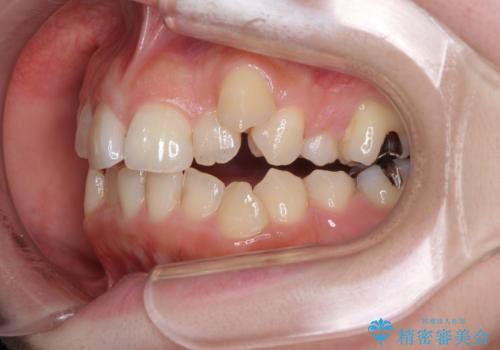

顕著な八重歯をインビザラインで治せるところまで改善

- 顕著な八重歯など、上下前歯のデコボコとスペースを気にして来院された患者様です。

八重歯改善には第一小臼歯の抜歯が必要であり、移動量が多いことから補助装置により八重歯を引き込むこととしました。

インビザラインでの治療をご希望であったので、インビザラインにて行うこととしましたが、右側前歯の改善にはワイヤー矯正が必要となる可能性があることをお伝えした上で治療を開始しました。

補助装置だけでなく、部分的にワイヤー矯正も使用しましたが、上下のスペースは改善しきれず、側切歯(前から2番目の歯)や顕著な八重歯は、インビザラインで治療するには限界があることがよく分かりました。

より良い仕上がりを希望される場合には、ワイヤー装置による矯正治療がお勧めとなります。